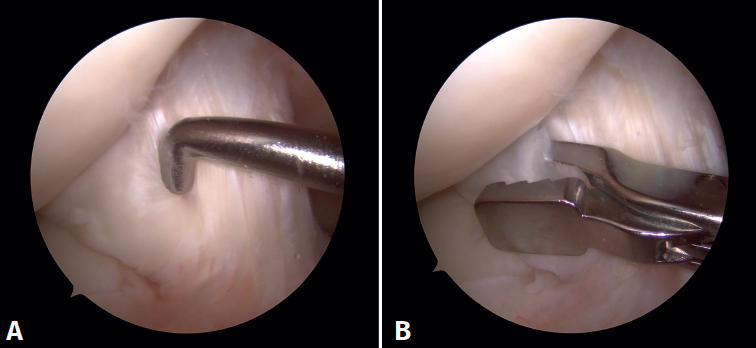

En ambos pacientes se realizó anestesia raquídea para realizar la cirugía y se utilizó manguito de isquemia a nivel del muslo. Se colocó al paciente en decúbito supino, utilizando un soporte en U en el tercio distal del muslo para la fijación de la extremidad. Se realizaron los portales artroscópicos habituales anterolateral y anteromedial, objetivando en la exploración diagnóstica de la rodilla la presencia de un ganglión localizado en el fascículo posterolateral del LCA (Figura 3) que, cuando se realizaban los movimientos de flexión y en posición de cuatro, se pinzaba en el espacio articular tibiofemoral externo. Para realizar la resección artroscópica del quiste se colocó al paciente en la posición “de cuatro”, facilitando la diferenciación anatómica de los fascículos anteromedial y posterolateral del LCA, tal y como proponen Hopper G et al.(4). Se realizó la disección y exéresis cuidadosa del quiste con una pinza basket, un terminal shaver de 4 mm y un terminal de ablación por radiofrecuencia (Figura 4). Al finalizar la resección del quiste, se realizó una nueva exploración dinámica de la rodilla, donde se evidenció la ausencia de pinzamiento entre el LCA, el cóndilo femoral y el platillo tibial lateral, a la vez que se comprobó la estabilidad del remanente del LCA (Figura 5).

En el postoperatorio se autorizó la movilidad y la carga progresiva con bastones según la tolerancia. En ambos pacientes la sintomatología dolorosa y las restricciones de movilidad articular se resolvieron completamente. No se realizó RM de control en ninguno de los dos casos.

Figura 5. Visión artroscópica desde el portal anterolateral. A: tras el desbridamiento se observa que no existe pinzamiento del espacio articular femorotibial lateral en posición “de cuatro” a 90° de flexión; B: palpación de la tensión del remanente del ligamento cruzado anterior.